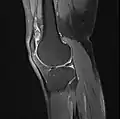

Imaging

MRI

Both anterior cruciate ligament (ACL) and posterior cruciate ligaments (PCL) are hypointense on both T1 and T2 weighted images of MRI. However, some high signal striations are often seen at the distal part of the ACL, making ACL higher intensity than PCL on MRI scans.[17]

- Knee MRI (PD TSE FS sagittal)

- Knee MRI (T1 TSE sagittal)

- Knee MRI (sagittal TSE FS)

- Knee MRI (sagittal T1 TSE)

- Knee MRI (coronal T2 TSE FS)

- Knee MRI (traverse PD TSE FS)

- Knee MRI osteoarthritis (sagittal TSE FS)

- Knee MRI osteoarthritis (sagittal T1 TSE)

- Knee MRI osteoarthritis (coronal T2 TSE FS)

- Knee MRI osteoarthritis (traverse PD TSE FS)

- Real-time MRI- Knee

- Knee MR